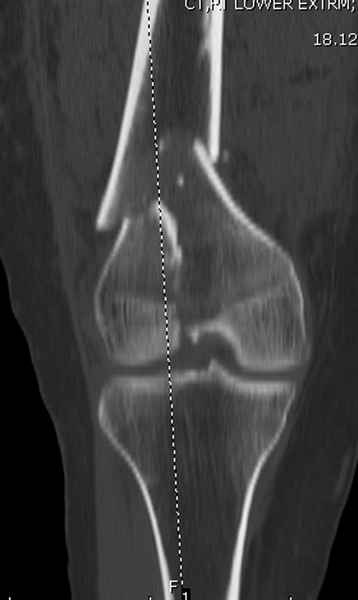

Приветствую всех коллег!!Во первых слева хотелось бы видеть четкую боковую проекцию а лучше КТ. По р-мам есть сомнения насчет повреждения суставной поверхности. При подобных переломах даже внутрисуставных без смещения хорошие результаты показал закрытый ретроградный остеосинтез универсальным бедренным стержнем Деост.Кстати при внутрисуставном переломе возможно применение вместо винтов стягивающих болтов!!(См. метод.Деост).При переломе справа также стержень Деост. Однако без открытия Вам не удастся устранить интерпозицию, только промучаетесь!Из минимального разреза удалите интерпозициб и фиксируйте стержнем. Причем универсальный стежень Деост позволяет фиксировать дистально минимум на трех уровнях!

Уважаемые коллеги! От имени Алексея Смирнова всем спасибо за обсуждение. Больной прооперирован. Снимки в приложении.